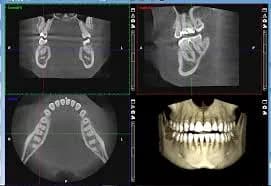

CBCT (Cone Beam Computed Tomography) interpretation involves a step-by-step analysis of all abnormal radiographic findings or features within a CBCT scan. The primary goal is to recognize and collect as much information as possible from the various image reconstructions. CBCT scans are mainly prescribed to assist in diagnosis, pre-surgical planning, and to assess the results of certain types of treatments or periodic evaluations. The analysis of the collected information from a CBCT scan can lead the clinician to a diagnosis or, more frequently, to a short list of possible diagnoses. Sources

Covers CBCT, IOPA, and OPG scans.